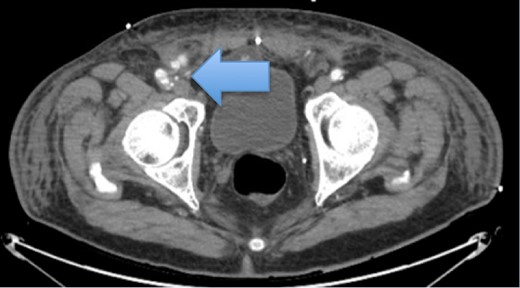

On the following day after the right transfemoral access approach, patient presents to ED with R groin and scrotal pain. On evaluation, severe tenderness on the R groin and scrotum was noted associated with worsening swelling and ecchymosis (Fig. 1). Vitals were within normal limits and initial hemoglobin of 12 g/dl. Ultrasound of the right groin showed a 6.3 × 4.0 × 4.9 cm hematoma (Fig. 2), his duplex ultrasound of bilateral testicle showed diminished blood flow on the right compared to the left (Fig. 3). CT of the pelvis revealed a pseudo-aneurysm on the R groin originating from the common femoral artery (CFA) measuring 2.5 × 1.4 cm and extending into the R inguinal canal, filled with hemorrhage and extension into the R scrotum that measures 13.7 × 6.4 × 6.6 cm (Fig. 4). During his clinical course, he has been hemodynamically stable in spite of drops in daily hemoglobin from 12, 8.9, 6.9, 5.9 g/dl, respectively, requiring two units of blood transfusions on hospital Day 3, and achieving a rise in hemoglobin to 8.6 g/dl. Patient then underwent an ultrasound-guided thrombin injection of the pseudo-aneurysm by the interventional radiologist without any complications and without any evidence of recurrence on ultrasound on the following day. Urology was consulted and offered no urologic interventions as his symptoms were improving. The scrotal and groin hematoma subsequently decreased in size. Patient was discharged on hospital Day 6 with aspirin and Plavix. Patient was followed up in clinic with no complains. On exam, there was a decreasing scrotal and R groin swelling/ecchymosis and improvement of penile swelling.

Pseudo-aneurysm from right CFA that extends obliquely measuring up to 2.5 × 1.4 cm. The pseudo-aneurysm appears to extend into the right inguinal canal, filled with hemorrhage extending into the inferior aspect of the right scrotum as well.